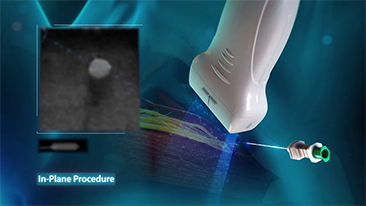

Quanto chiaramente puoi visualizzare il fegato?

Per le lesioni focali epatiche, come l'emangioma o il tumore al fegato, l'imaging di contrasto a ultrasuoni svolge un ruolo importante. La tecnologia di imaging di contrasto Ultra-wideband non-linear UWN+ consente di ottenere una migliore penetrazione, un rapporto contrasto-tessuto pi├╣ elevato con un indice meccanico pi├╣ basso e un'osservazione del tempo di perfusione pi├╣ lunga.